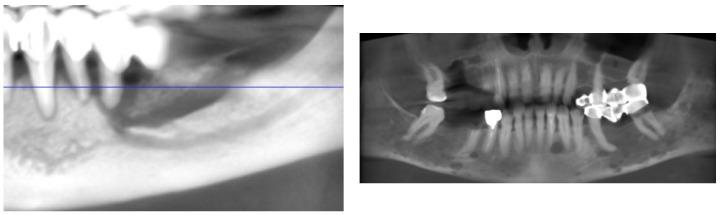

This review systematically examines the oral complications associated with conventional and novel anti-cancer therapies. It highlights that while molecularly targeted agents including monoclonal antibodies targeting the vascular endothelial growth factor and its receptor, the epidermal growth factor receptor, tyrosine kinase inhibitors, and immune checkpoint inhibitors tend to exhibit a lower overall toxicity profile compared to traditional cytotoxic chemotherapeutics, they are nonetheless linked to significant oral adverse events. These complications encompass inflammatory mucosal reactions known as mucositis, salivary gland dysfunction leading to a sensation of dryness in the mouth, taste alterations referred to as dysgeusia, and, critically, medication-related osteonecrosis of the jaw. In particular, bone-modifying agents such as bisphosphonates and denosumab disrupt bone remodeling and the formation of new blood vessels, thereby increasing the susceptibility to osteonecrosis of the jaw, especially following invasive dental procedures. The review delineates the multifactorial pathogenesis underlying these toxicities, which involves direct cell toxicity, impaired wound healing, and secondary infections. Furthermore, it emphasizes the importance of pre-treatment dental evaluation and preventive strategies including patient education, prophylactic dental care, and the integration of adjunctive therapies such as laser therapy and autologous platelet concentrates to mitigate these adverse effects. The analysis advocates for interdisciplinary collaboration between oncologists and dental professionals to optimize management protocols, enhance treatment adherence, and ultimately improve the quality of life for oncology patients undergoing anti-cancer therapy.